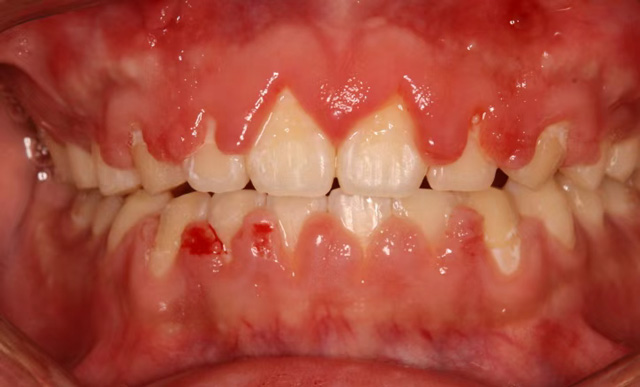

为了拥有整齐的牙齿和舒展的笑容,很多人选择了口腔正畸治疗。在与牙套亲密接触的过程中,有些人发现自己的牙龈变大变鼓了,按一按也不痛,还挺瓷实。这种情况被称为“牙龈增生”。

最常见的原因是第一个,口腔清洁做得不好。固定矫正治疗期间,由于托槽和弓丝容易挂住食物,需要在餐后做好刷牙等口腔清洁工作,如果清洁不到位,大量的食物残渣会留在牙齿和牙龈上,为细菌提供了温床,长期这样会引起牙龈炎,直至牙龈增生。

杨艳(副主任医师):牙龈增生主要发生在固定托槽矫正人群中。以我的个人经验,十年多前牙龈增生是比较多的,随着患者口腔清洁意识的提高,还有矫治器的更新换代,现在在成年人中已经不常见了,在儿童和青少年里发生得更多一些。

至于原因,一方面是因为儿童对刷牙方法掌握得不好,或是没有做到每次吃完东西都清洁牙龈,另一方面也和激素有关,处于生长发育期的青少年由于激素相对紊乱,更容易出现口腔内的感染。

杨艳(副主任医师):牙龈增生对于矫正治疗没有明显的影响,它主要是影响美观,特别严重的可能会影响到咀嚼。

轻度的牙龈增生,一般在拆除托槽后可以逐步恢复。如果矫正治疗尚未结束,我们除了给患者强调要好好刷牙以外,还会给予药物牙膏和涂抹外用药物进行消炎治疗,并根据需要进行龈上洁治(洁牙),龈下洁治(刮除龈下结石)。